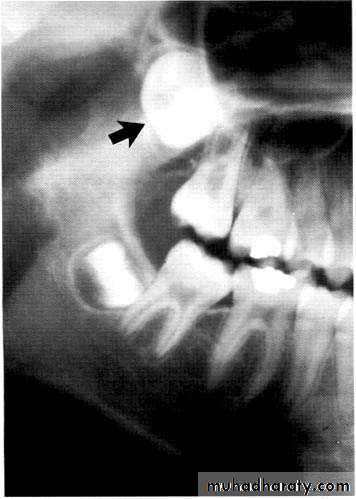

Paramolar blocking the eruption of 3rd molar.

MesiodensDistomolars(4th molar)